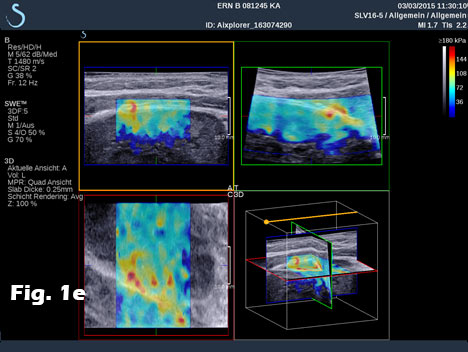

We report on the incidental finding of a 70 y/o patient presenting with an indolent cervical swelling and mass. Clinical examination and laboratory data were not conclusive. In the figure sequence B mode ultrasound and shear wave elastography revealed a 43 mm mass lesion with peripherally stiffer tissue (a) with thrombosis in statu nascendi of jugular vein shown by B mode (b) and also by contrast enhanced ultrasound (c) and shear wave elastography (d). 3D shear wave elastography confirmed the circumscript peripherally stiffer cervical mass (e). 3D SWE added complementary information for a better delineation of the distribution of increased stiffness, following the fibrous capsule around the nerve. SWE also showed feasibility to demonstrate stiffer tissue within jugular vein. 3D techniques allowed improved documentation of the anatomical volume including the tumour and surrounding vessels [(1-3)]. Histologically the nerve tumour schwannoma was proven.

On Aixplorer®, ShearWave™ Elastography has also been implemented on a linear 3D wobbling probe. Leveraging on the ultrafast imaging capabilities of Aixplorer, the acquisition of both grayscale imaging and SWE™ imaging in a three-dimensional volume takes a few seconds, depending on the size of the volume, and data can be analysed and reprocessed retrospectively in the full volume. Thanks to the high frequency broad bandwidth transducer (5 to 16 MHz), high quality images can be reconstructed in the axial, the transverse and the coronal planes. The operator can choose to navigate in the volume acquired using a customizable multislice or multiplanar display. The probe was mainly designed to be used in breast imaging. Here we reported on the first use of 3D SWE in nerve tumours. 3D SWE added complementary information for a better delineation of the stiffer fibrous capsule around the nerve.

Figure 1:B mode ultrasound and shear wave elastography revealed a 43 mm mass lesion with peripherally stiffer tissue (a) with thrombosis in statu nascendi of jugular vein (b), also shown by contrast enhanced ultrasound (c) and shear wave elastography (d). 3D shear wave elastography confirmed the circumscript peripherally stiffer cervical mass (e).